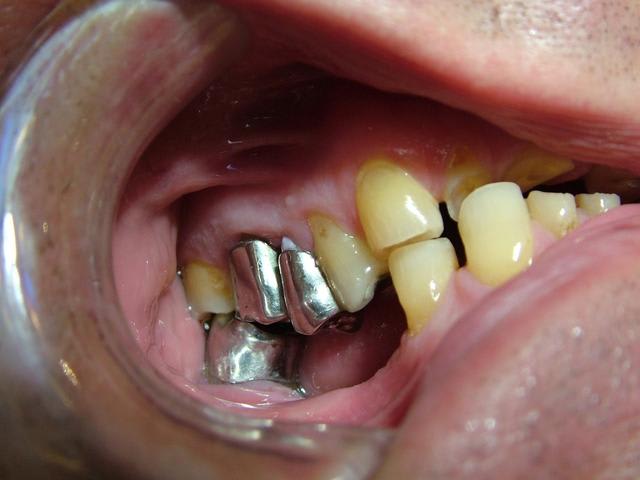

ce serait sympa de voir une photo en bouche qui sera plus parlante.

oui il y a un calage postérieur avec des dents dans tous les sens et des molaires complétement déviées

est ce la bonne occlusion?

Merci pour toutes les réponses qui m'ont aidé à réfléchir au cas et surtout ne pas me précipiter sur mon plan de traitement stupidement. J'ai revu le patient il y a qq jours et je devais ce jour là lui faire la présentation du plan de traitement. Je lui ai expliqué que son cas était tellment complexe que je n'avais pas pour le moment de solution thérapeutique valable car je n'avais pas encore traité ce type de cas. Le patient a fort bien compris et j'en ai profité pour prendre des radios buccales ; en effet la mise sur occluseur que j'avais sur les précédentes photos était fausse. Le patient "occluse" différement. Voir les nouvelles photos jointes. Il y a très peu de contact antérieur ; j'ai bien demandé une dizaine de fois au patient de se mettre en occlusion pour arriver au même résultat que l'on voit sur les photos. Le patient a bien sur du mal à avoir un occlusion stable.

Il est vrai que la DV me semble conservé car il y a un calage postérieur côté droit et côté gauche.

Je mettrai la semaine prochaine les photos des modèles avec la nouvelle occlusion.

Pour l'instant je serai plutôt d'avis de lui remonter de 1 à 2 mm la DV avec une plaque de surélévation ( plaque pendant 2 à 3 mois) pour voir si les ATM supportent et faire des élongations coronaires sur les dents antérieures que l'on conservera.